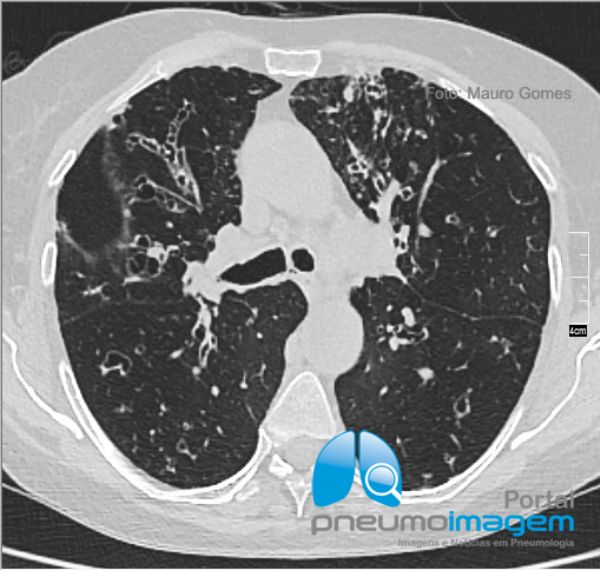

Na Aspergilose Broncopulmonar Alérgica (ABPA) as bronquiectasias são centrais. É possível ainda observar nesse corte tomográfico na região dos ápices vários nódulos centrolobulares. Na ABPA há eosinofilia (>500/mm³), IgE muito elevada (>1000 UI/ml), IgG anti-Aspergillus e IgE específica (RAST) contra Aspergillus também elevadas. A ABPA faz parte do diagnóstico diferencial da asma de difícil controle.

In bronchopulmonary Allergic Aspergillosis (ABPA) bronchiectasis is central. It is also possible to observe in this tomographic section in the apical region several centrilobular nodules. In ABPA there is eosinophilia (> 500 / mm³), very high IgE (> 1000 IU / ml), anti-Aspergillus IgG and specific IgE (RAST) against Aspergillus also raised. ABPA is part of the differential diagnosis of difficult-to-control asthma.